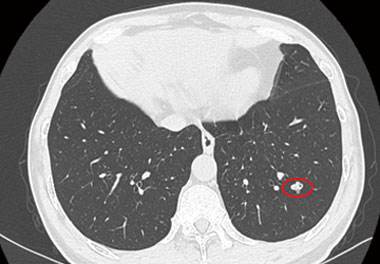

HD Fluorescence Endoscopic System uses advanced optical design and signal processing technology that go far beyond the traditional concept of endoscopy. Combining with fluorescent imaging agent, i.e., ICG, the fluorescence imaging system can enable the users to switch the modes freely among Standard White Light Mode, Fluorescence Mode, Dark Fluorescence Mode and Black/White Fluorescence Mode by pressing the buttons on camera head at any time during surgery. Allowing real-time lymphatic system tracking, liver tumor/segment & pulmonary nodule/segment identifying, biliary tree mapping, tissue perfusion evaluation and precise tumor boundary mapping intra-operatively, our system provides surgeons with more accurate, more secure and more effective surgical options.